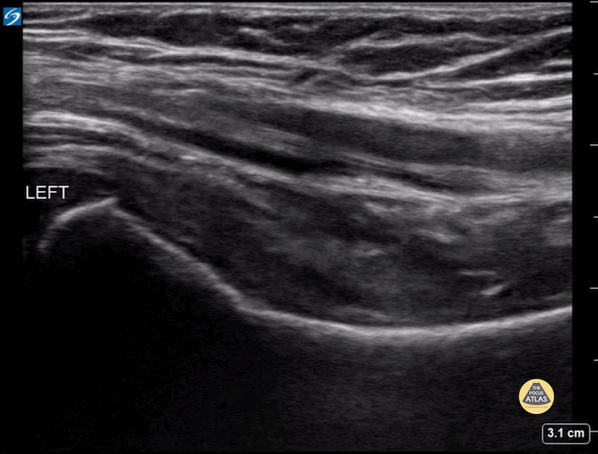

5 year old male presented with a left leg limp, assessment of the affected hip joint did not reveal a pathologic effusion. Contributor: Zach Boivin, MD, @ZachBoivinMD